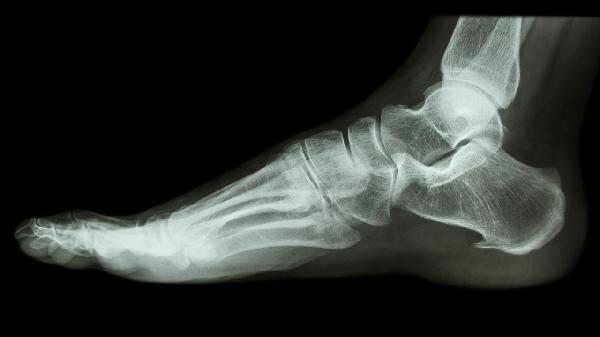

脚上楔骨骨折怎么办

脚上楔骨骨折可通过休息制动、冰敷消肿、药物治疗、物理治疗、手术治疗等方式处理。楔骨骨折通常由直接暴力、间接暴力、肌肉牵拉、骨质疏松、病理性骨折等原因引起。

对于移位明显的关节内骨折、开放性骨折或保守治疗失败的情况,需考虑手术治疗。常用术式包括切开复位内固定术,使用螺钉或钢板对骨折块进行牢固固定。术后仍需配合石膏外固定,并定期复查X线片观察骨折愈合情况。手术治疗能实现解剖复位,最大程度恢复足部功能。